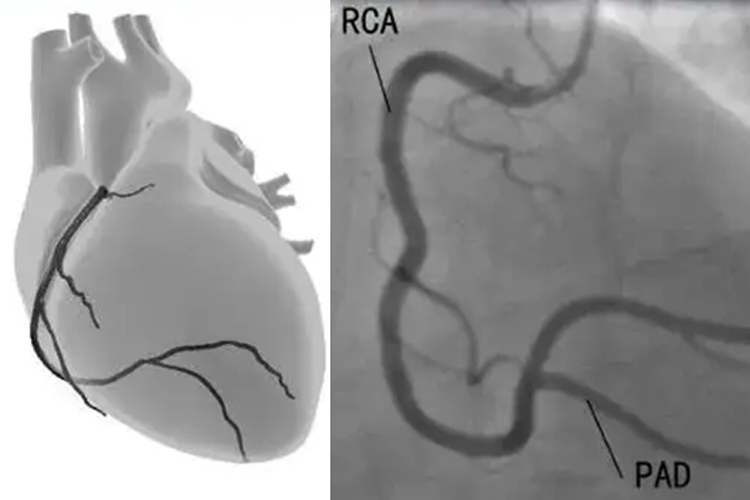

心脏造影,又称冠状动脉造影,是一种用于检查冠状动脉状况的重要医疗手段。一般情况下,心脏造影的结果出来的时间会因多种因素而有所不同,快则30分钟到1小时出结果,慢则需要1-2天,甚至更长时间。

- 不过,如果是在常规的门诊或住院检查中,心脏造影的结果可能需要1-2天才能出来。这是因为造影检查完成后,影像资料需要由专业的医生进行详细分析和评估,包括对冠状动脉的狭窄程度、病变位置、血管形态等多个方面进行综合判断。同时,还可能需要与其他检查结果进行对比和综合考虑,以给出最准确和全面的诊断报告。